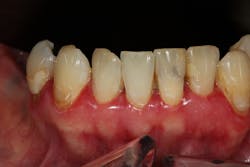

If these methods are ineffective, surgical treatment is warranted. Conventional surgical treatment includes the use of surgical blades, knives, and high-speed burs to remove the excess gingival tissue. Dental lasers such as diodes, 10.6 micron CO2, erbium YAG, erbium chromium YAG, and Nd:YAG lasers have also been implemented to remove excess soft tissue.3

Another laser that has been used to treat gingival enlargement and gummy smiles is a 9.3 micron CO2 laser (Solea from Convergent Dental; figure 2a). Unlike other lasers, the Solea laser has the capabilities of removing both soft and hard tissue, precise cutting accuracy due to control of both laser beam power and size, and the ability to cauterize inflamed tissue (figures 4c and 4d). Conventional instrumentation—such as blades, knives, and high-speed burs—can often lead to bleeding after surgical removal when the tissue is inflamed. With this type of CO2 laser, sutures and/or surgical dressing are often not needed.